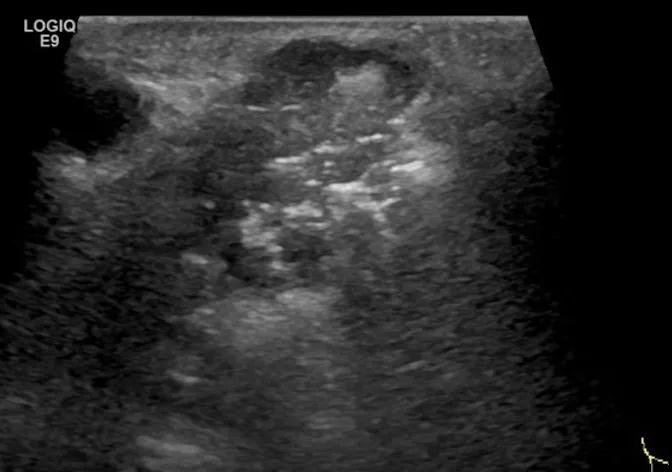

第四例是胸腺癌化妆包,术后、化疗之后淋巴结转移,肿块范围巨大,99mm*61mm,边界不清,呈浸润状,肿块包绕颈动脉,颈内静脉压闭,症状明显。由于患者放化疗也不敏感、血供非常丰富,于是采取多点姑息性消融。姑息性消融后未实现完全消融,病灶大片坏死,肿胀疼痛得到明显的缓解,后续患者未再来复查。

(病例4图例)